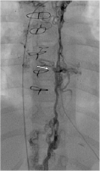

The Fontan operation represents the last of multiple steps that are offered a wide range of congenital cardiac lesions with a single ventricle (SV) physiology. Nowadays this surgical program consists of a total cavopulmonary connection (TCPC), by anastomosing systemic veins to the pulmonary arteries (PAs), excluding the right-sided circulation from the heart. As a result of imaging, surgical, percutaneous, and critical care improvements, survival in this population has steadily increased. However, the Fontan physiology chronically increases systemic venous pressure causing systemic venous congestion and decreased cardiac output, exposing patients to the failure of the Fontan circulation (FC), which is associated with a wide variety of clinical complications such as liver disease, cyanosis, thromboembolism, protein-losing enteropathy (PLE), plastic bronchitis (PB), and renal dysfunction, ultimately resulting in an increased risk of exercise intolerance, arrhythmias, and premature death. The pathophysiology of the failing Fontan is complex and multifactorial; i.e., caused by the single ventricle dysfunction (diastolic/systolic failure, arrhythmias, AV valve regurgitation, etc.) or caused by the specific circulation (conduits, pulmonary vessels, etc.). The treatment is still challenging and may include multiple options and tools. Among the possible options, today, interventional catheterization is a reliable option, through which different procedures can target various failing elements of the FC. In this review, we aim to provide an overview of indications, techniques, and results of transcatheter options to treat cavopulmonary stenosis, collaterals, impaired lymphatic drainage, and the management of the fenestration, as well as to explore the recent advancements and clinical applications of transcatheter cavopulmonary connections, percutaneous valvular treatments, and to discuss the future perspectives of percutaneous therapies in the Fontan population.